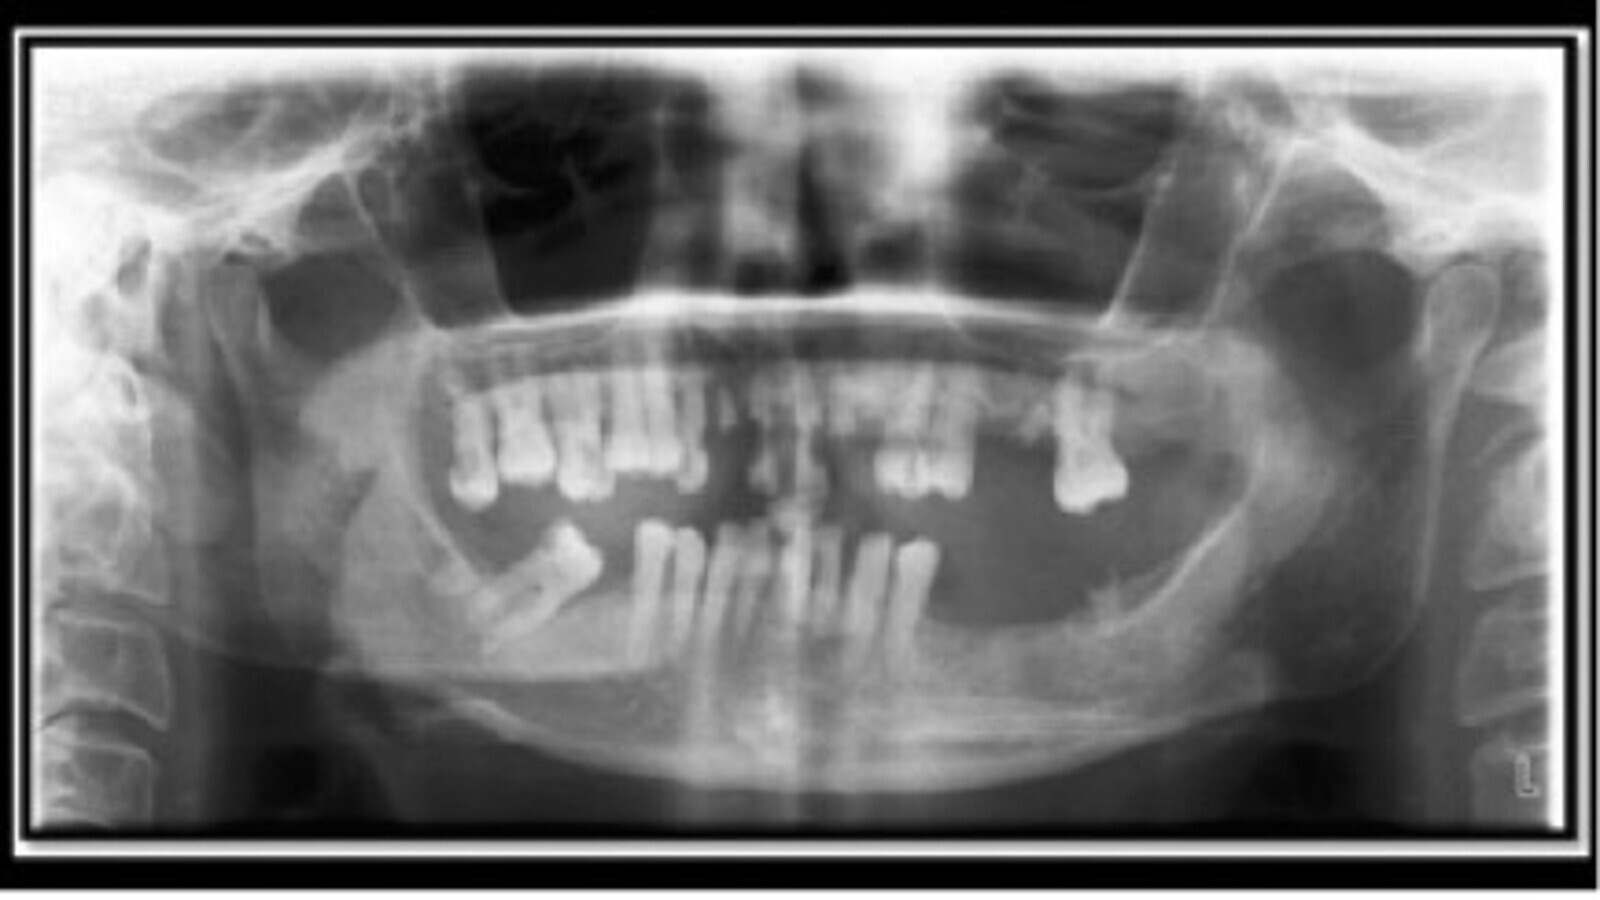

El dentista debe realizar una evaluación exhaustiva de toda la cavidad oral del paciente y, si detecta anomalías como úlceras, bultos, manchas rojas o blancas, puede recomendar pruebas adicionales, como una biopsia, para obtener un diagnóstico definitivo. Fotos: SECIB

Así, cuando un paciente acude a una revisión odontológica, el dentista debe realizar una evaluación exhaustiva de su cavidad oral que incluye las mejillas, los labios, la lengua, el paladar y las encías. Y si detecta anomalías como úlceras, bultos, manchas rojas o blancas, puede recomendar pruebas adicionales, como una biopsia, para obtener un diagnóstico definitivo.

En sus primeras etapas, el cáncer oral puede pasar desapercibido. Hay que prestar atención a los síntomas y signos de alarma, como una mancha de color blanco o rojo en la boca, o una pequeña úlcera que no se cura en unas dos semanas. Otros síntomas incluyen dolor o dificultad para tragar, hablar o masticar. El dolor de oído persistente en un solo lado también puede ser una señal de advertencia.